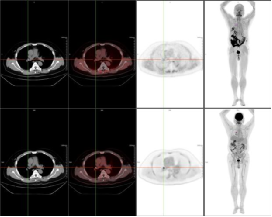

例一:患者53岁男性,肝内胆管癌术后7月余,八周期化疗后复查。图像第一排为FAPI显像;第二排为FDG显像。

肝顶部及残肝右叶病灶FDG显像未见明显显示,而FAPI显像明显显示,CT密度均未见明显异常。

且较本院增强MR及FDG显像新发现肝左叶病灶;右肺门淋巴结FDG显像及FAPI显像均代谢增高,高度怀疑转移灶。